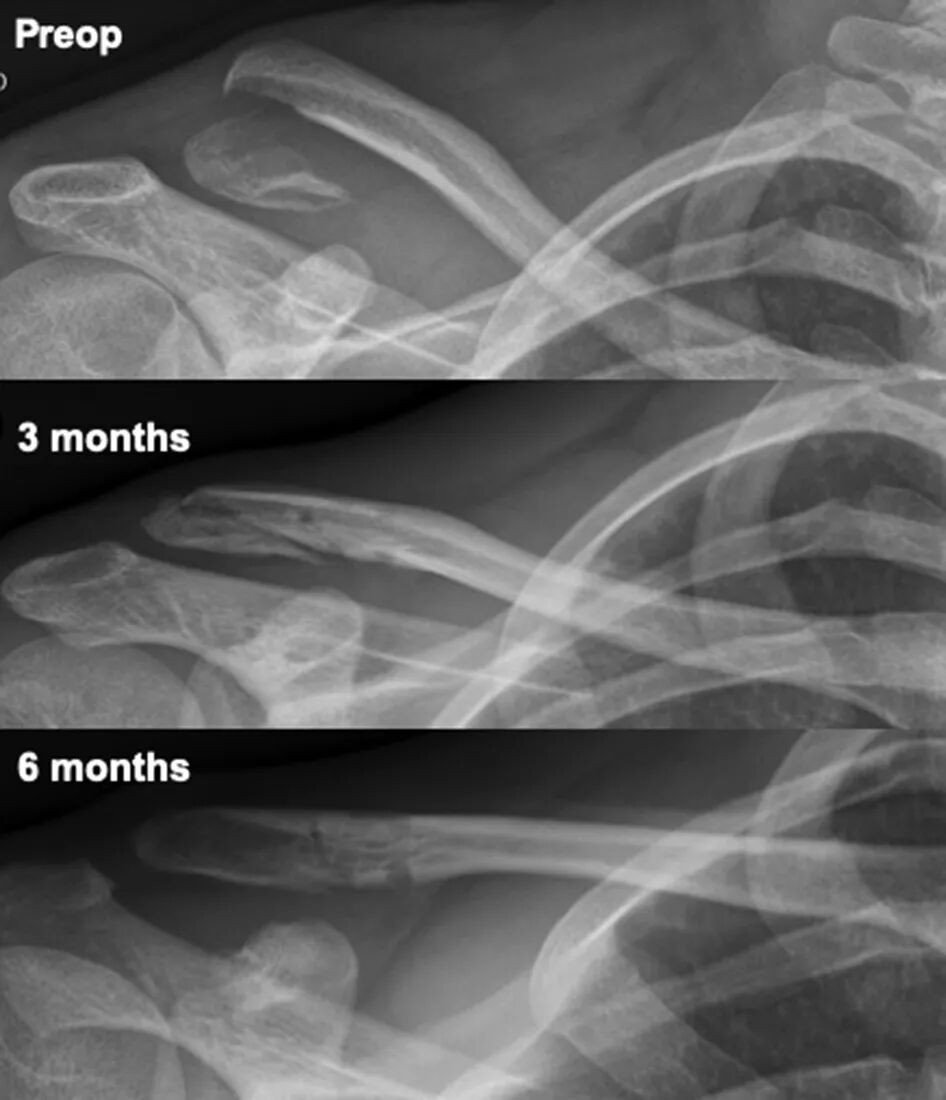

• Radiographic Healing: Regular radiographic follow-up is essential to monitor fracture healing and guide progression through rehabilitation phases.